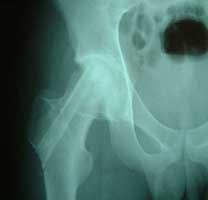

股骨头缺血性坏死MRI显示坏死区                  微创手术方法,采用隧道减压刮除死

BMP植入,异体骨支撑,恢复形态       手术后24个月X线片,关节塌陷未加重,关节功能良好,无疼痛